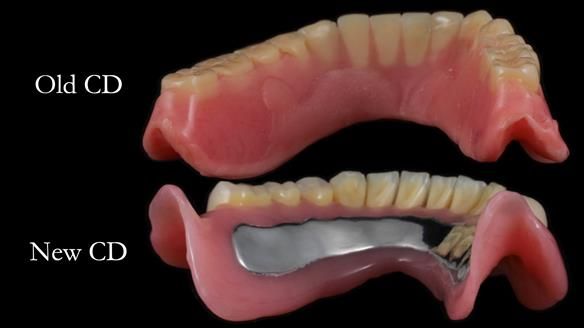

Welcome to Newsletter 62. In this edition, I walk through the process of removing 5 upper anterior teeth, adding to an existing upper RPD, followed by creating and fitting metal based complete dentures for Rafique, a 71 year old man.

Inadequate upper and lower dentures – thickened with reline material. Almost unwearable.

The detailed clinical situation and treatment process are outlined below, with clinical work provided by me and technical work by Rowan Garstang. The treatment spanned 12 months, involving removing 5 upper anterior teeth, adding to an existing upper RPD, followed by creating and fitting metal based complete dentures.